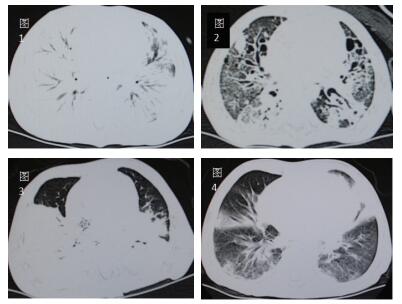

初期表现为单侧节段性实变为主(3/9),双侧散在片状影或大片融合灶(6/9),伴有部分肺气肿。快速进展至双侧大片肺实变(5/9))或者“白肺”(4/9),伴胸腔积液或者气胸、纵隔气肿。恢复期多见背段、双下肺散在片状影残留(7/9),部分发展为肺纤维化及肺坏死灶(2/9)。典型影像学改变见下图。

| 图 1 图 1、2分别示例7急性期,两肺几乎完全实变;恢复期,肺纤维化及坏死空洞图。图 3、4分别示例4急性期,背段大面积融合实变伴肺气肿;恢复期,树芽状增生,毛玻璃样变。 |